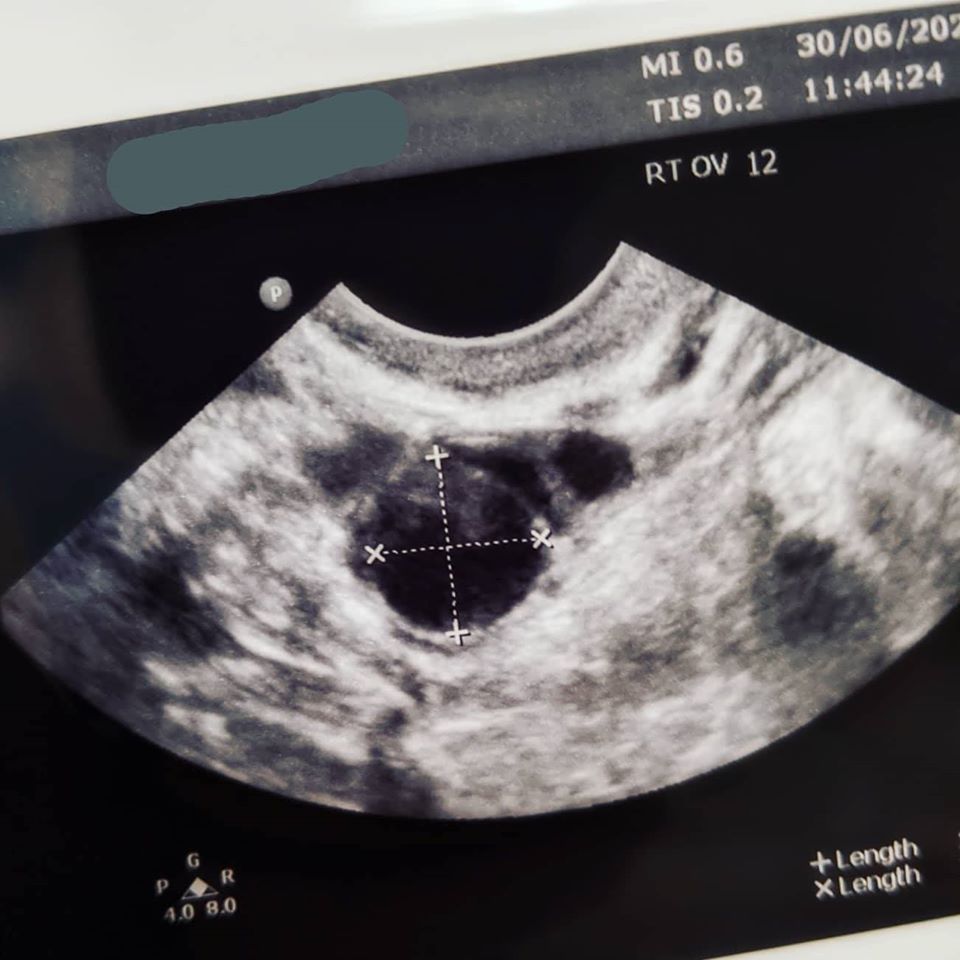

I had two follicles growing on my right ovary and none on my left. In most menstrual cycls a follicle will grow on an ovary and get bigger until it ruptures at ovulation and releases the egg. Follicles are good.

On CD10 I had one measuring 13.5mm and one measuring 12mm.